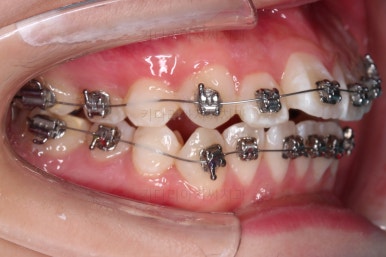

이번 환자분이 선택하신 장치는 엠파워 메탈이라고 하는 자가결찰 메탈장치에요.

자가(스스로) 결찰(철사를 잡아주는 캡이 달려있는) 메탈(금속성분의) 장치라는 뜻인데요.

메탈이라고 옛날 장치가 아니라 자가결찰인지 아닌지가 훨신 중요하답니다.

부산덧니교정 치료방법은 발치교저이며 윗니를 훨씬 많이 당겨줘야하기 때문에 미느스크류를 보조적으로 사용했어요.

장치 부착 직후의 모습인데요.

웃을 때의 느낌, 장치 때문에 입이 튀어나오는 정도 등 참고해주세요.